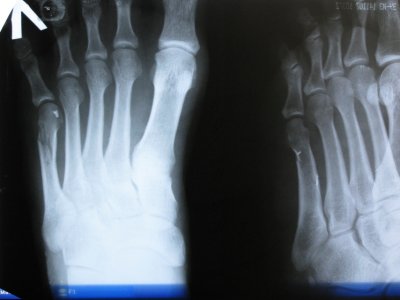

Здравствуйте! Скажите, пожалуйста, есть ли улучшения в сростании 5 плюсн. кости? Первый снимок сделан в день травмы, 2-ой - через 20 дней.

08.05.2010.JPG 28.05.2010.JPG

По мне, так то же самое))

Особой разницы не вижу, да и рано еще.

Правильно сказали, фиксация гипсом 4 недели. Срастается перелом дольше, до 3-х мес. Вы спрашивали о динамике сращения, на картинках которые вы вывесили она не видна. Что вижу, то и говорю.